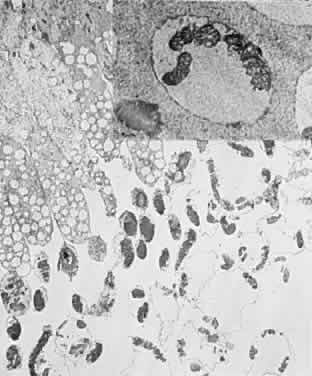

PATHOLOGIC FINDINGS

Clinicopathologic correlations of photic retinopathy have been reported by several investigators.16,75,76,144–146 Aware of prior studies by others on rats,25,147–150, Tso and coauthors reported the first of their series, performed on monkeys in 1972.75 They believed that the difference in their observations versus those published on rats might be related to the species of animal studied. Tso and coworkers created a model of chronic photic maculopathy through exposure to an indirect ophthalmoscope and found that significant changes were produced the first week after exposure, but a distinct maculopathy became evident only after an extended follow-up (5 months). They also described three stages in which this maculopathy occurs: initial degeneration in the first week, macrophagic response between the first week and first month, and repair and regeneration between the first and fifth month. Tso and associates also noted that, in the reparative phase, scarlike lesions noted clinically corresponded to proliferation of the RPE on a cellular level and, despite changes in the RPE, the overlying photoreceptors had regenerated. These clinicopathologic correlations led to more studies of macular response to light-induced injury. Histopathologic study of photic retinopathy in the human eye caused by exposure to light from the operating room microscope was reported by Green and Robertson in 1991.144 They describe the light and electron microscope findings of operating room microscope-induced maculopathy in a patient's eye after exposure to the light source for 60 minutes, 72 hours before enucleation for an iris melanoma (Figs 5 through 8). Findings in this acute form of photic retinopathy occurred mainly at the level of the RPE and photoreceptor layer and included the following: localized necrosis of the RPE; loss of the apical villi, plasma membranes, and cytoplasmic organelles of the RPE cells; extrusion of the retinal pigment epithelial pigment granules; and extensive disruption of the outer lamellae of the photoreceptors. Swollen mitochondria were present within the photoreceptor inner segments. Although this study was designed to address the issue of acute light-induced retinal damage, the additional finding of thinned retinal pigment epithelial cells, which apparently had migrated under injured RPE cells, suggests that a reparative process had already begun. The findings of Green and Robertson are consistent with those of Jaffe and coworkers reported in primates.146

Fig. 5. Light-microscopic appearance of an area of junction between phototoxic lesion (to the right) and normal unaffected retina and retinal pigment epithelium (to the left). In the lesion, the retina is edematous. An amorphous material is observed in the area of disrupted outer segements of the photoreceptors and the subretinal space. (Green WR, Robertson DM: Pathologic findings of photic retinopathy in the human eye. Am J Ophthalmol 112:520, 1991)

Fig. 6. Light-microscopic appearance of photic retinopathy with edematous outer retina and the edematous irregularly thickened retinal pigment epithelium. Most of the swelling involves the photoreceptor layer where an amorphous material largely replaces the outer segments. The photoreceptor nuclei appear relatively intact. (Green WR, Robertson DM: Pathologic findings of photic retinopathy in the human eye. Am J Ophthalmol 112:520, 1991)